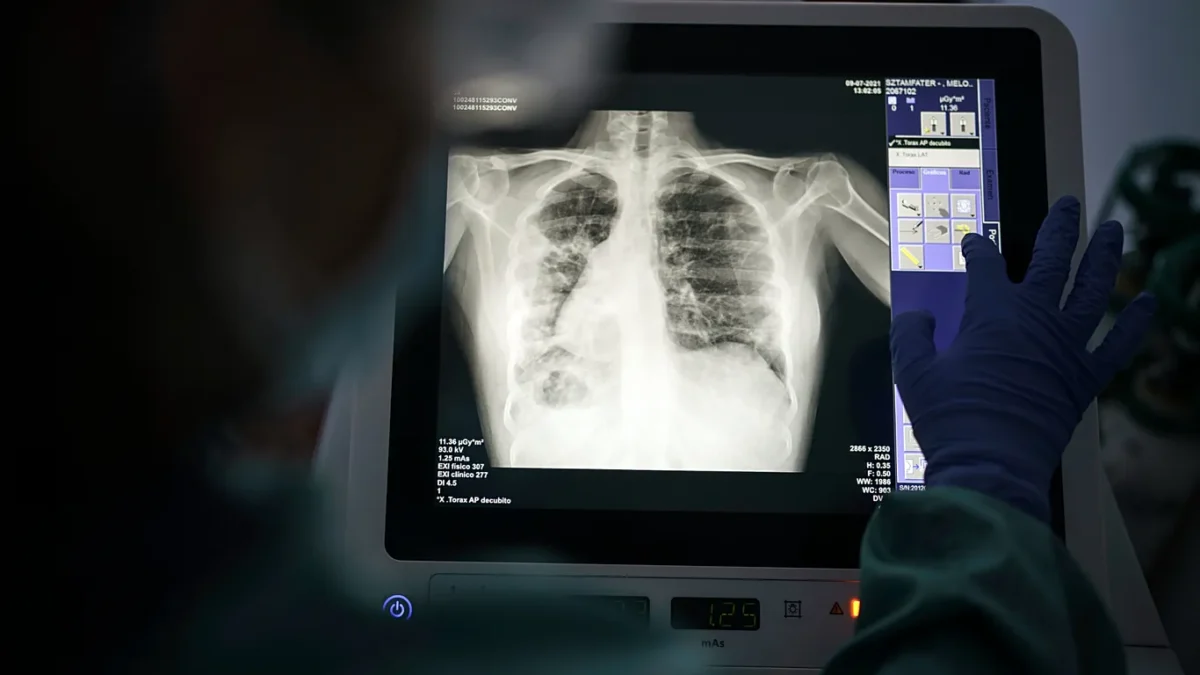

توفي طبيب عراقي اليوم السبت، إثر إصابته بمرض الحمى النزفية (حمى القرم-الكونغو النزفية)، ليكون الحالة الثانية التي تسجلها محافظة كركوك في غضون 72 ساعة. وأكدت مصادر طبية محلية “أن الطبيب، الذي كان يعمل في إحدى المؤسسات الصحية بالمحافظة، أصيب بالمرض قبل أيام، وتدهورت حالته الصحية بسرعة رغم محاولات العلاج، مما أدى إلى وفاته”.

وفي وقت سابق من الأسبوع، “سجلت كركوك أربع إصابات مؤكدة بالحمى النزفية، توفي اثنان منها، بينما لا يزال المصابان الآخران يتلقيان العلاج في مركز متخصص في حالة مستقرة”. وبحسب مصادر في دائرة صحة كركوك، “تضمنت الحالات الأخيرة مواطناً من جنوب المحافظة وموظفاً حكومياً آخر، وقد تم اتخاذ الإجراءات اللازمة لعزلهم ومتابعة المخالطين”.

وفي إطار التصدي للفيروس، دعت دائرة صحة كركوك المواطنين “إلى الالتزام بالإجراءات الوقائية، مثل تجنب الذبح العشوائي، والذهاب إلى المراكز الصحية عند ظهور أعراض الحمى الشديدة أو النزيف”، مشيرة إلى “أن الكشف المبكر يزيد من فرص الشفاء ويحد من تفشي المرض”.

العراق.. جواميس كركوك تنذر بأزمة صحية وتحذير من تفشي “الحمى النزفية”

حذر ناشطون ومتخصصون بالبيئة في محافظة كركوك العراقية من “وجود بؤر لتجمعات الجواميس في مدخل المحافظة”.

وبحسب “شفق نيوز”، أشار الخبراء إلى أن “هذه المجاميع تشكل خطرا حقيقيا لنقل الفيروسات وخاصة الحمى النزفية”.

وقال الخبير البيئي عبد الرحمن علي إن “المنطقة الواقعة قرب ناحية تازة في كركوك، وبالتحديد أسفل الجسر عند مدخل المحافظة، بجانب التكية الكسنزانية، أصبحت مأوى لمجاميع من الجواميس الأمر الذي قد يسهم في انتشار الأمراض خاصة في ظل غياب الرقابة البيئية والصحية الكافية”.

وأضاف علي أن “الجواميس هناك تموت يوميا بالعشرات وهي بؤر ناقلة للحمى النزفية”.

يُذكر أن الحمى النزفية هي “مرض فيروسي خطير ينتقل من الحيوان إلى الإنسان، خاصة من خلال لدغات القراد أو ملامسة دماء حيوانات مصابة”.

وفي العام الماضي، “سجل العراق نحو 200 إصابة مؤكدة بالمرض، توفي منها 26 حالة”، وفقاً لبيانات وزارة الصحة العراقية.